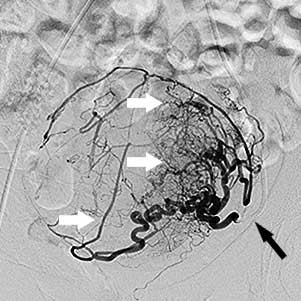

Ендоваскулярний хірург робить прокол шкіри голкою в паховій складці або руці та, потрапивши в артерію, вводить туди тонку (1,5–2 мм), спеціально зігнуту трубку — катетер. Оскільки процедура малоболісна, використовується лише місцева анестезія, яку доповнюють препаратами для легкого медикаментозного сну. Хірург під рентгенівським контролем проводить катетер артеріями до матки — спеціальна апаратура дозволяє стежити за переміщенням катетера всередині тіла. Катетер по черзі підводиться до правої та лівої маткової артерії. Далі виконується артеріограма — введення в маткову артерію спеціальної контрастної речовини, видимої під рентгеном, що дозволяє "побачити" фіброміому і підтвердити правильне розташування катетера.

Права маткова артерія:

чорна стрілка - катетер, білі стрілки -

розширені артерії вузла

Ліва маткова артерія: